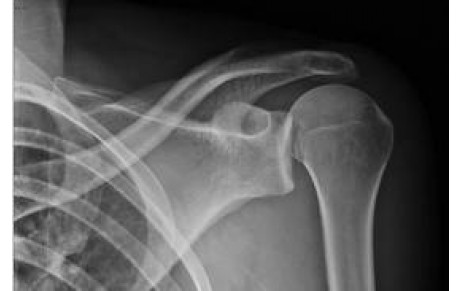

Au delà des deux nouvelles défaites des Seniors hier au Havre, malgré deux bons matchs, la liste des blessés s'est encore allongée... Guillaume Cuffel est victime d'une luxation de l'épaule, avec arrachement des ligaments (blessure identique à celle...